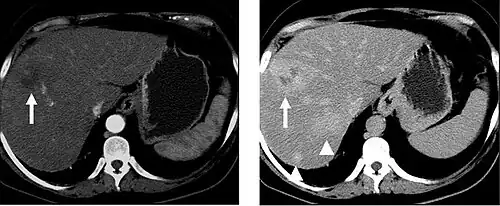

Non-contrast CT scans Figure 1a (left) and 1b (right) are of limited use for the differentiation of soft tissue structures. However, materials like blood, calcium (renal stones, vascular atherosclerosis), bone, and pulmonary parenchyma are highly visible and can usually be adequately assessed with non-contrast CT. For example, in the abdomen and pelvis, there are several indications for non-contrast imaging. These include: evaluation of renal calculi; assessment for gross intra-abdominal hemorrhage; and post-endostent volume measurements. In addition, non-contrast images are often obtained in conjunction with contrast enhanced images in evaluating potential renal transplant donors and in the evaluation of the pancreas (in combination with contrast phases). Of note, dual-energy CT and the development of virtual "non-contrast" images (VNC imaging) may ultimately obviate the combination scans. Additionally, CT angiography examinations performed for pathologies like aneurysms and dissection are frequently performed in conjunction with non-contrast imaging. The non-contrast images facilitate the differentiation of active extravasation or acute bleeding from vascular calcifications.